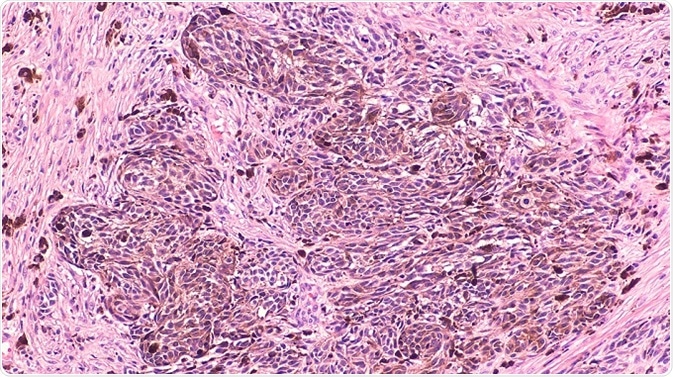

Melanoma is a destructive form of skin cancer and treating advanced-stage melanomas is difficult due to the fact that tumors develop resistance to most of the therapies at this stage, including drugs targeting oncogenic BRAFV600E. Moreover, strong responses to immune checkpoint therapies are observed in only one-third of melanoma patients.

In addition to fibroblasts, immune cells such as B cells, T cells, macrophages, and neutrophils are also present in the tumor stroma. Cross-talk between malignant and immune cells happens either directly through cell–cell interactions or by soluble mediators such as cytokines and growth factors.

The presence of melanoma-infiltrating T cells is correlated to a favorable prognosis, but the importance of tumor-infiltrating or tumor-associated B (TAB) cells is not well documented. TAB cells account for up to ~33% of all infiltrating immune cells and their frequency can be correlated to a better prognosis in primary melanoma, as well as to shorter overall survival (OS) and increased metastasis.